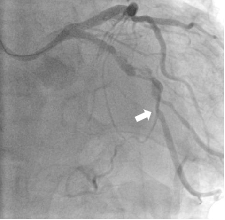

Baseline angiography showed 80% stenosis and calcification of the mid-left circumflex branch (LCX) (Fig. 1-2)

A TruePhysio® pressure microcatheter was advanced in the LCX but could not go any further due to severe stenosis and calcification. The location it reached is shown by the arrow in Fig. 3.

The resting Pd/Pa was 0.64 in this location.